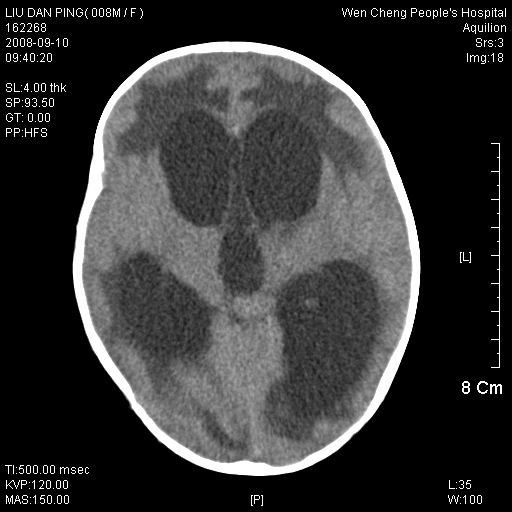

以下是引用卜一在2008-9-10 16:21:00的发言:[br]髓母细胞瘤伴梗阻性脑积水!支持![br]髓母细胞瘤特点:—般直径大于3.5cm,位于后颅凹中线之小脑蚓部。累及上蚓部的肿瘤延伸到小脑幕切迹之上,ct平扫肿瘤多呈均匀一致的高或等密度病灶,增强检查呈均匀一致的强化。病灶中有小坏死时,平扫亦可呈不均匀之混杂密度,注药后有增强。[br]

以下是引用zjzjr在2008-9-10 15:09:00的发言:[br]髓母细胞瘤伴梗阻性脑积水.